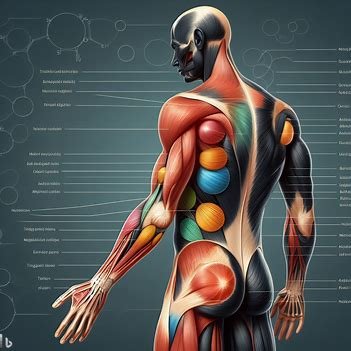

الكثير منا في هذه الايام يتعرض لآلام في نقاط معينة من الجسم وتعب وإرهاق مستمر وصعوبة في التركيز وألم في العضلات، كلنا نتساءل ما السبب؟ قد تكون مصاباً بالفايبروميالجيا التي تعتبر حالة مزمنة تتسم بالألم المزمن والتعب الشديد والحساسية المفرطة في الجسم. حيث يعاني الأشخاص...